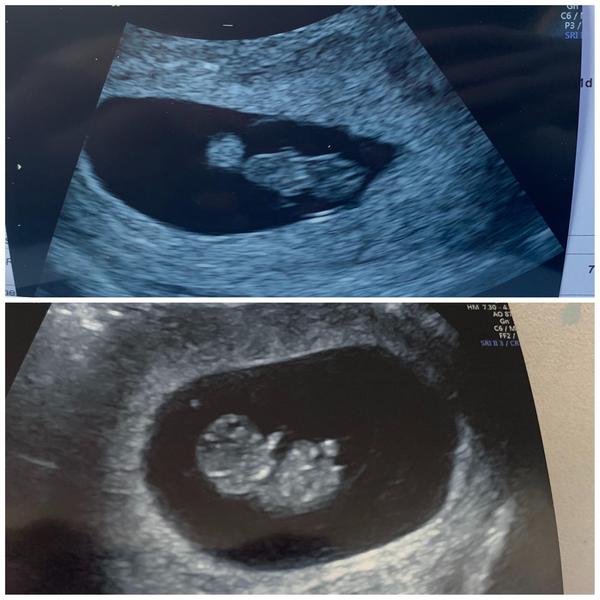

Congrats! I've been to WTWW a few times. They've always been great. Scans are relatively short, about 5-10 mins but they are thorough and walk you through everything. My local clinic send you a link to an app where all the photos are and there's normally around 20. I think you get a few printed to take away as well.

This was mine as 9+4, so definitely baby-like at that point!

These are my scan pics. Top one obviously 7 weeks 😂